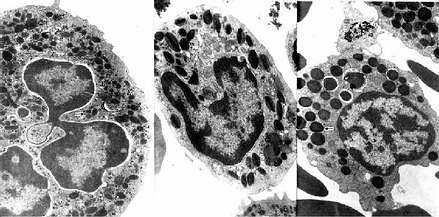

人三种粒电镜像

图5-5 人三种粒电镜像 ×17800

左图:中性粒细胞(白求恩医科大学尹昕、朱秀雄教授供图)

中图:嗜酸性粒细胞 左图:嗜碱性粒细胞

↑特殊颗粒,(

嗜天青颗粒 )嗜天青颗粒

中性粒细胞的胞质染成粉红色,含有许多细小的淡紫色及淡红色颗粒,颗粒可分为嗜天青颗粒和特殊颗粒两种。嗜天青颗粒较少,呈紫色,约占颗粒总数的20%,光镜下着色略深,体积较大;电镜下呈圆形或椭圆形,直径0.6~0.7μm,电子密度较高(图5-4,5-5),它是一种溶酶体,含有酸性磷酸酶过氧化物酶等,能消化分解吞噬的异物。特殊颗粒数量多,淡红色,约占颗粒总数的80%,颗粒较小,直径0.3~0.4μm,呈哑铃形或椭圆形,内含碱性磷酸酶吞噬素溶菌酶等。吞噬素具有杀菌作用,溶菌酶能溶解细菌表面的糖蛋白

2.嗜酸性粒细胞 嗜酸性粒细胞(eosinophilicgranulocyte,eosinophil)占白细胞总数的0.5%-3%。细胞呈球形,直径10~15μm,核常为2叶,胞质内充满粗大(直径0.5~1.0μm)、均匀、略带折光性的嗜酸性颗粒,染成桔红色(图5-2)。电镜下,颗粒多呈椭圆形,有膜包被,内含颗粒状基质和方形或长方形晶体(图5-4,5-5)。颗粒含有酸性磷酸酶、芳基硫酸酯酶、过氧化物酶和组胺酶等,因此它也是一种溶酶体。

3.嗜碱性粒细胞 嗜碱性粒细胞(basoophilic granulocyte,basophil)数量最少,占白细胞总数的0~15。细胞呈球形,直径10-12μm。胞核分叶或呈S形或不规则形,着色较浅。胞质内含有嗜碱性颗粒,大小不等,分布不均,染成蓝紫色,可覆盖在核上(图5-2)。颗粒具有异染性甲苯胺蓝染色呈紫红色。电镜下,嗜碱性颗粒内充满细小微粒,呈均匀状或螺纹状分布(图5-4,5-5)。颗粒内含有肝素和组胺,可被快速释放;而白三烯则存在于细胞基质内,它的释放较前者缓慢。肝素具有抗凝血作用,,组胺和白三烯参与过敏反应。嗜碱性粒细胞在组织中可存活12-15天。